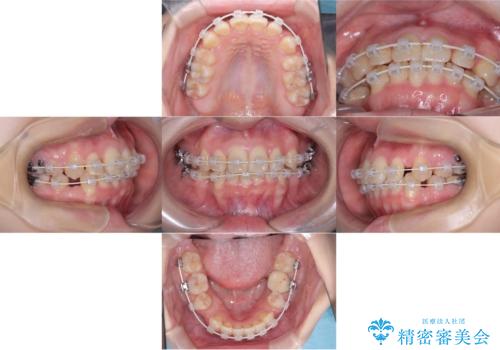

- 「歯のデコボコ、八重歯、口ボコが気になる」を主訴に来院された患者様です。

上下左右4番(4本)の歯を抜歯しワイヤー矯正で治療を行いました。

計4本の抜歯を行い、歯のデコボコと口元がすっきりし、大変ご満足していただけました。